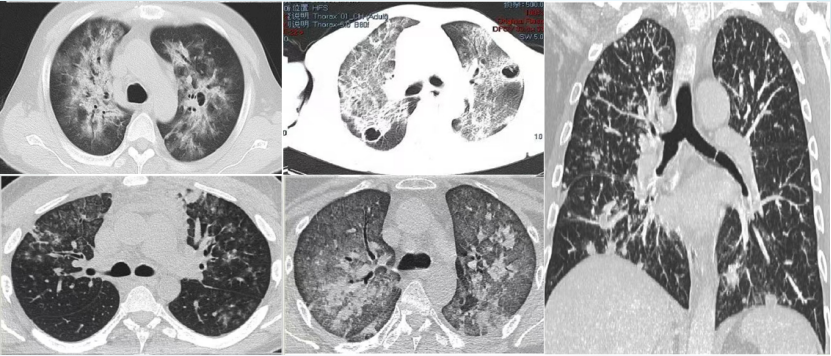

图片

6  肺孢子菌肺炎患者的影像学

3. 影像学特点

1)近心端对称性分布的弥漫性磨玻璃病灶,支气管清晰可见

2)空气潴留征

3)胸膜下月弓征

4)晚期可见气囊病变,纤维化

5)罕见以肺内单发或多发肉芽肿结节为影像表现。